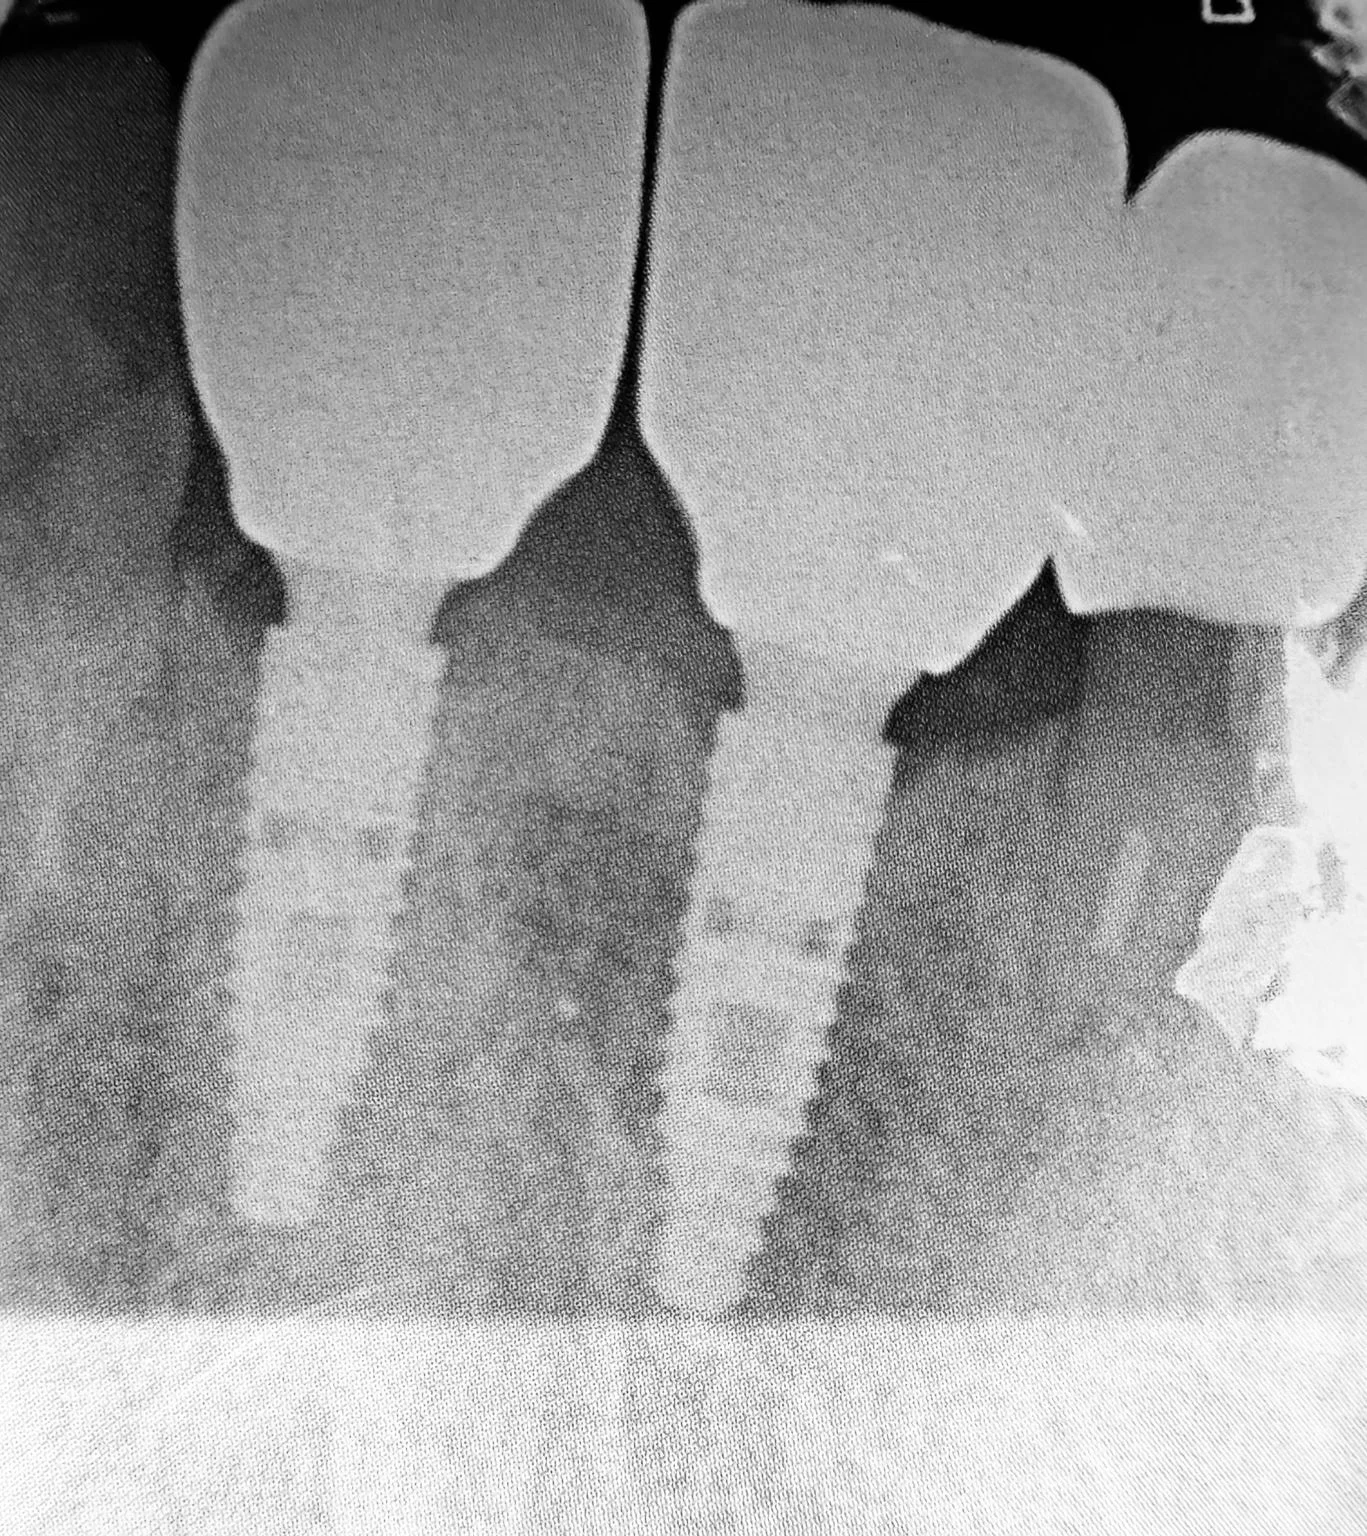

Estrazione, Rigenerazione Ossea e Riabilitazione Implantare

Riabilitazione post estrazione con impianto